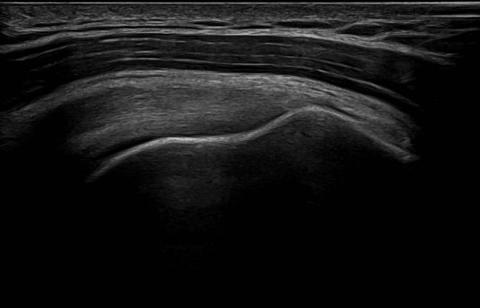

Shoulder ultrasound is a precise, real-time imaging technique that allows us to quickly assess the possible causes of your discomfort. For many conditions, a shoulder ultrasound is the gold standard for rotator cuff tear and bursitis, and it can also guide injections of steroid or other medication into the joint or bursae. I provide same day results for most scans, so you won't be left waiting and worrying.

During your specialist shoulder ultrasound, you will sit in a supportive chair while I carry out the scan. Depending on which shoulder needs assessing and your movement comfort, I may work from in front of or behind you. I'll gently assist you in moving your shoulder into a variety of positions, so we can get the best views of all tendons and structures. Sometimes, I assess your shoulder movement dynamically, in real-time, giving further insights into the source of your pain.

Shoulder ultrasound is an effective way to visualise tendons, muscles, and bursae as you move, helping to pinpoint causes like frozen shoulder or rotator cuff tears. - Guidance for treatment